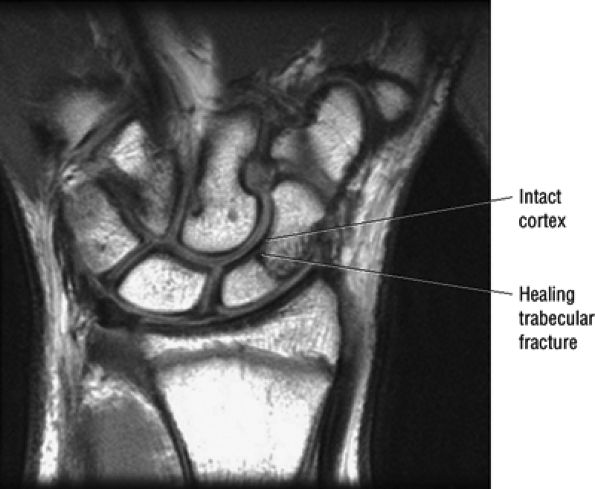

FIGURE 10.36 Triangular Fibrocartilage.

similar to the meniscus. Tears of the TFC are visualized as defects or gaps in the substance of the TFC. Tears of the membranous portion of the TFC manifest as a gap with a diastasis between the two ends of the bow-tie. The scapholunate and lunotriquetral ligaments are harder to visualize on sagittal images. However, tears of the dorsal or volar components of these ligaments, or ganglion cysts extending through these ligaments, are occasionally seen and further characterized on sagittal images.